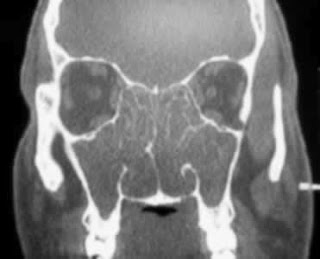

![]() |

| Coronal |

| Normal |